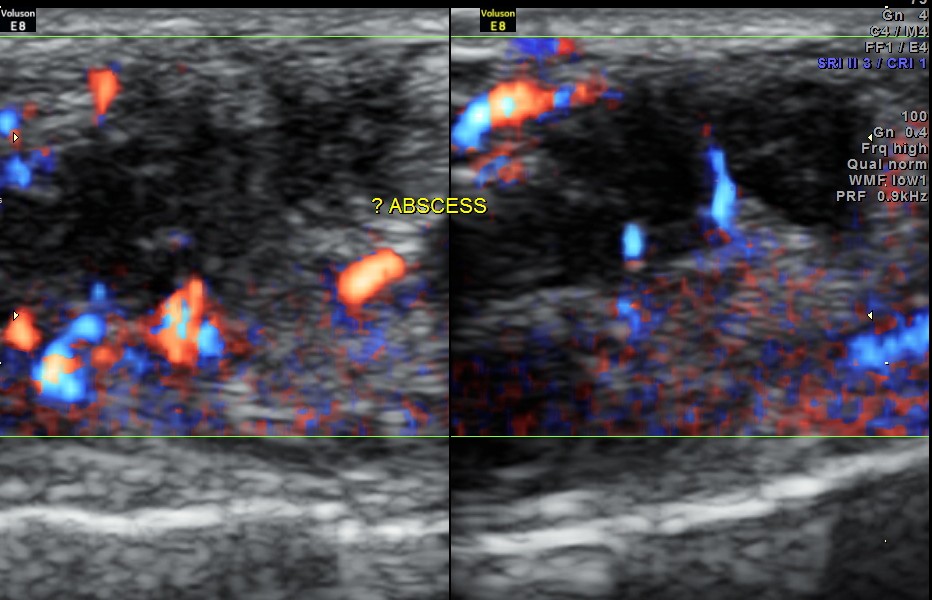

An indistinct hypo echoic mass was seen under a tendon and was well away from the surface of the bone .

Colour Doppler showed increased vascularity all around .